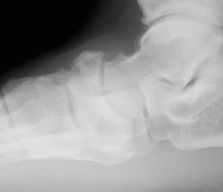

Xray

Displaced navicular stress fracture